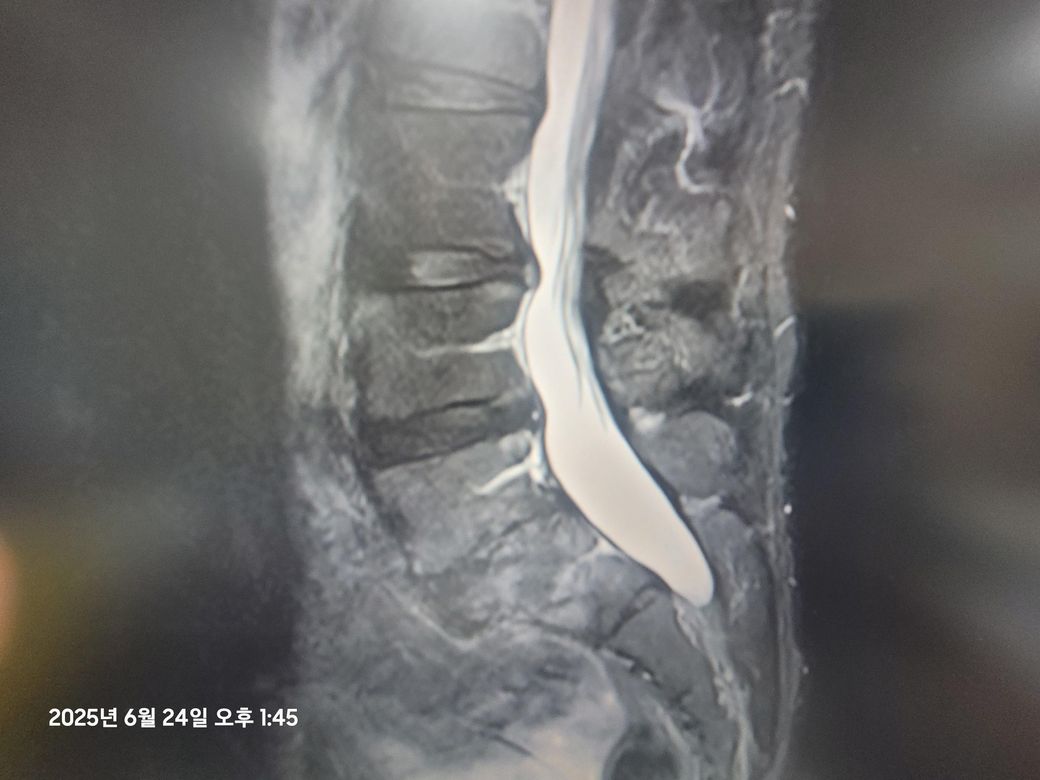

• 3번 째 사진